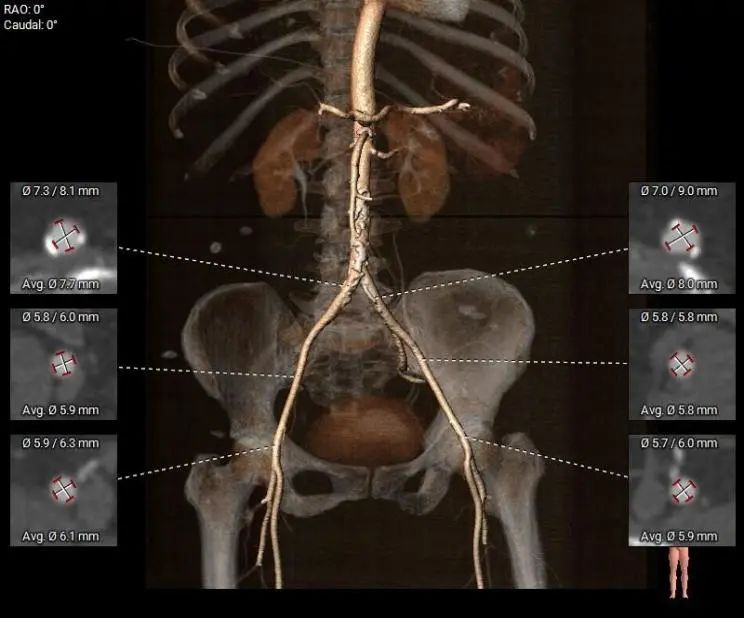

外周入路

腹主动脉及左右髂总动脉有附壁钙化分布,左右髂外动脉及左右股动脉血管内径稍细,余血管内径可